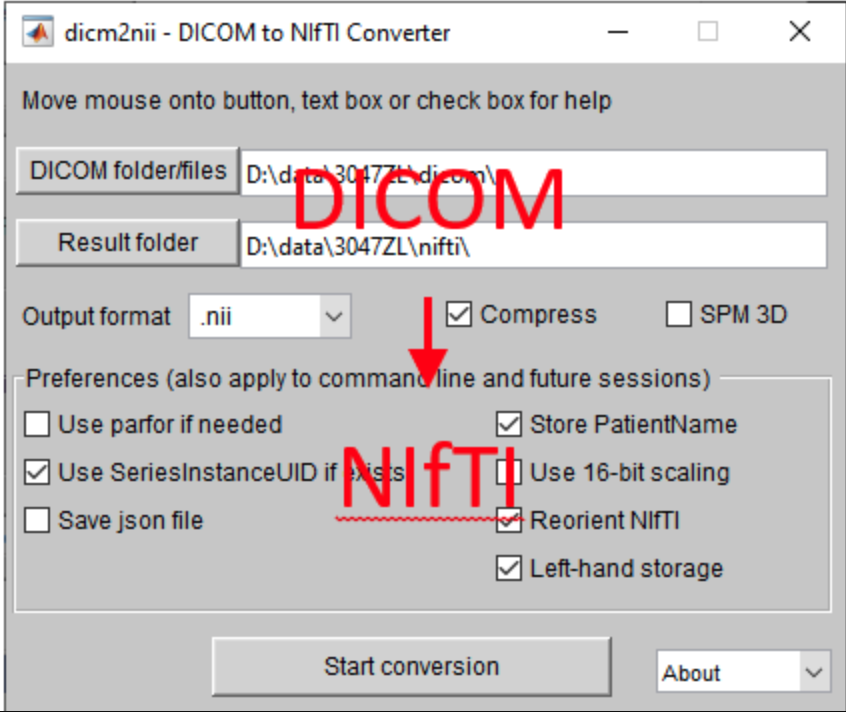

图形界面版

图形界面版需要先下载 MRICron。在上图左边设置好输出文件的命名格式,输出文件夹等参数,把dcm文件夹拖到右边空白处即可完成转换。

MRICron的下载链接,软件示意图👇